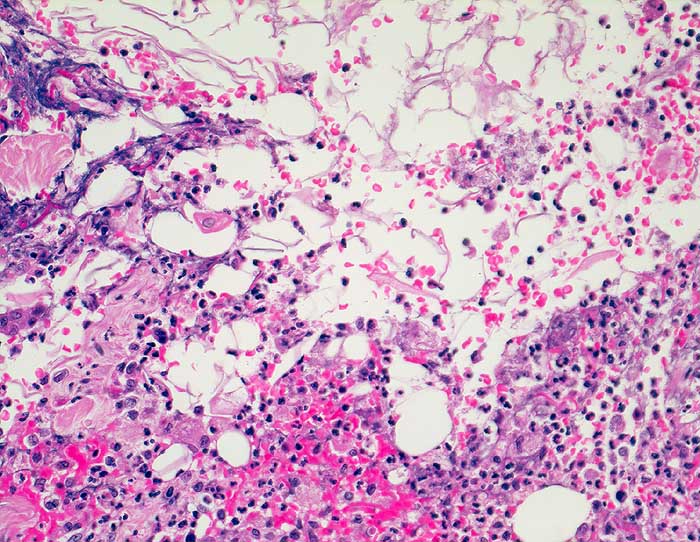

Rupturierte Epidermoidzyste

Die Zystenwand ist vollständig entzündlich zerstört. Das Entzündungsinfiltrat besteht aus Granulozyten und Histiozyten durchmischt mit Blut. In der oberen Bildhälfte sind zahlreiche Hornlamellen erkennbar.

Grosses, seit 5 Jahren bestehendes, entzündlich verändertes Atherom am Rücken

Histologie

200